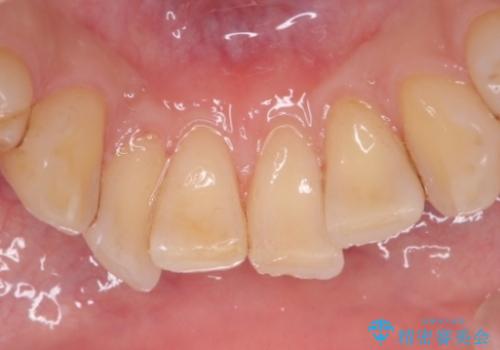

PMTCによる着色除去

- 着色が気になるとのことで来院された。

着色だけでなく、歯石やバイオフィルムの除去、ハイドロキシアパタイト配合のトリートメントで仕上げ磨きまで行います。